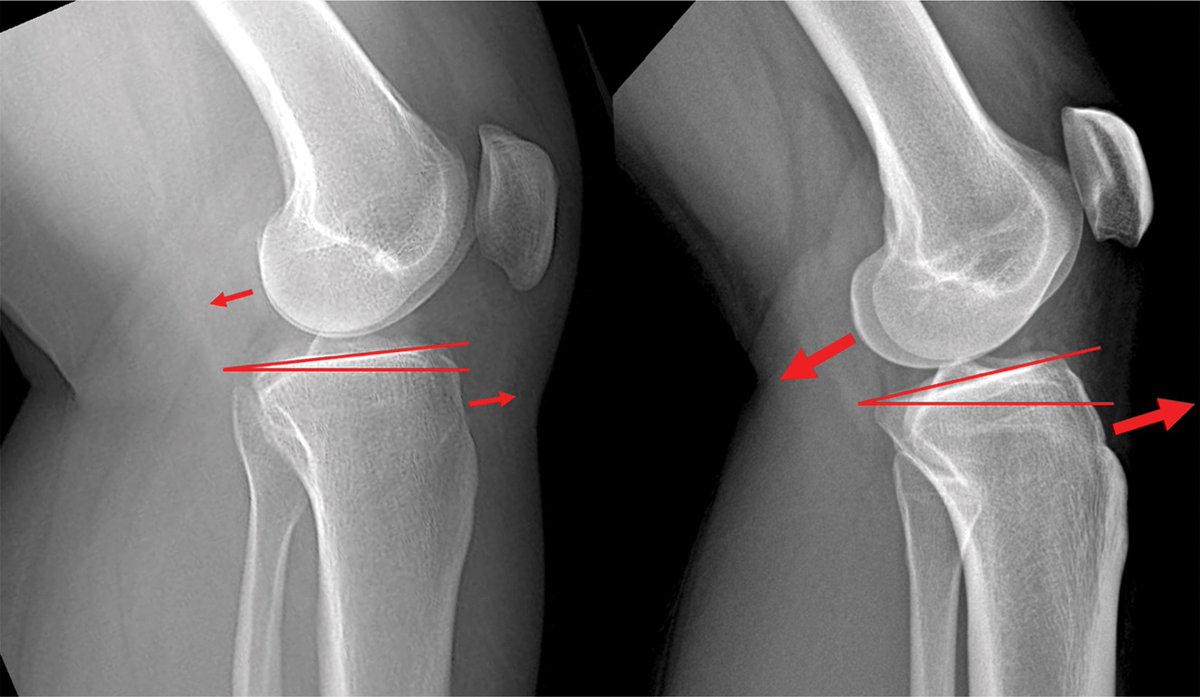

AAOS Appropriate Use Criteria: Case Study on Return to Play to Pre-Injury 2 Level Following Anterior Cruciate Ligament Injury bit.ly/4eo6Gmu Dr. Richard Ma, MD